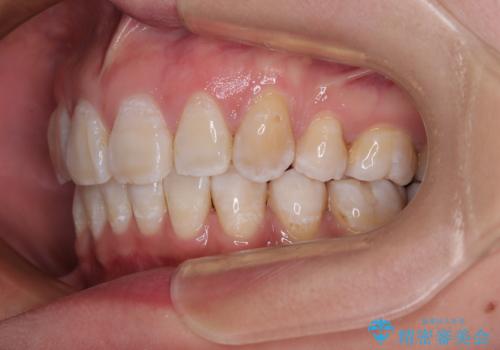

上顎前突で口が閉じにくい ワイヤー装置での抜歯矯正

- 上顎歯列の出っ歯を気にして来院された患者様です。

骨格的に上顎歯列が前方位にあり、口元の突出感が顕著な状態で、上下左右の第一小臼歯4本を抜歯して、ワイヤー装置での抜歯矯正を行うこととしました。

ご本人がびっくりするくらい劇的に口元の突出感が改善され、大変満足のいく仕上がりとなりました。